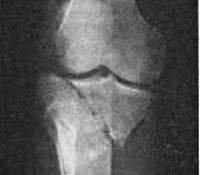

В момент травмы появляется резкая боль в колене. Колено увеличено в объеме, при переломе внутреннего мыщелка может выявляться варусная деформация, при переломе наружного – вальгусная. Движения и опора резко ограничены. Наблюдается патологическая подвижность при боковых движениях в суставе. Аккуратно надавливая на мыщелки одним пальцем, обычно можно четко определить зону максимальной болезненности. Имеется выраженный гемартроз, который иногда становится причиной резкого расширения сустава и нарушений местного кровообращения.

Основным методом инструментальной диагностики является рентгенография коленного сустава. Рентгеновские снимки выполняют в двух проекциях. В абсолютном большинстве случаев это позволят достоверно установить не только факт наличия переломов, но и характер смещения отломков. При неоднозначных результатах рентгенографии пациента направляют на КТ коленного сустава. При подозрении на сопутствующее повреждение мягкотканных структур (связок или менисков) назначают МРТ коленного сустава. Иногда переломы мыщелков сопровождаются сдавлением нервов и сосудов, при подозрении на повреждение сосудисто-нервного пучка (повреждение сосуда и повреждение нерва) назначают консультации сосудистого хирурга и нейрохирурга.